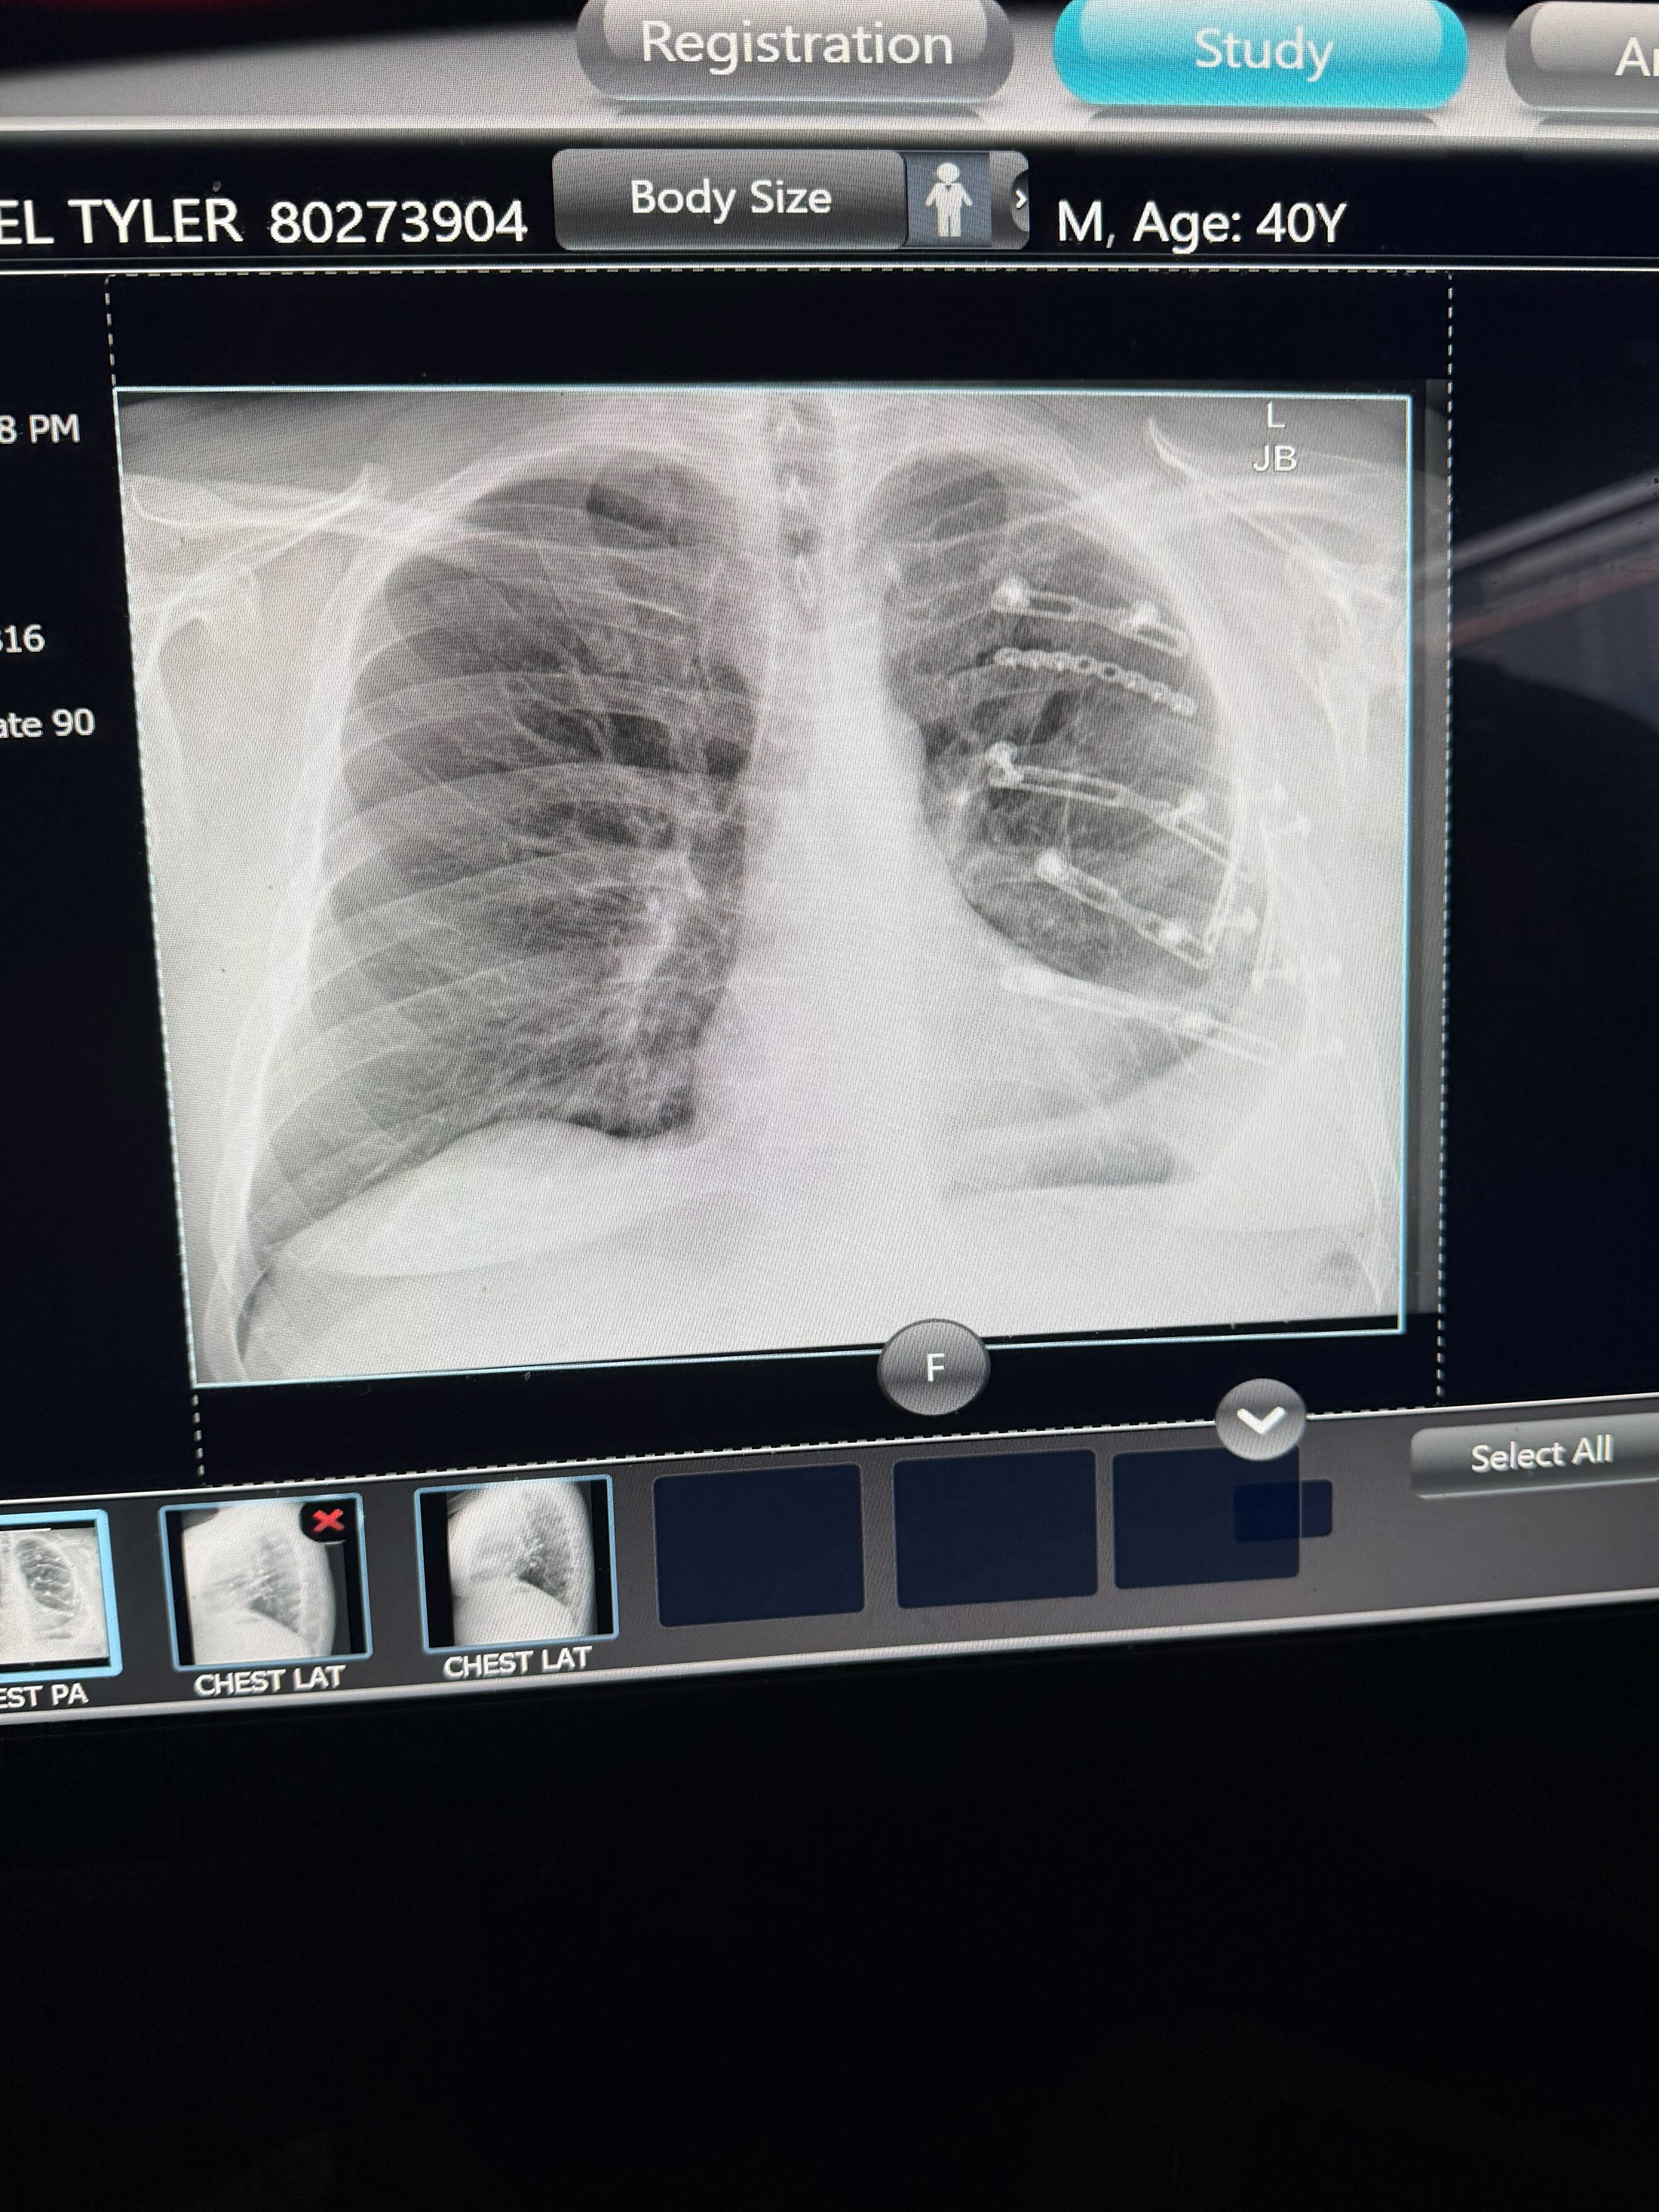

But on the horse ride back to the trailhead, Freel was thrown from his horse. He crashed to the icy ground at full speed, and though he knew he was hurt instantly, nobody quite knew the extent of his injuries at the time, which turned out to be extremely severe.